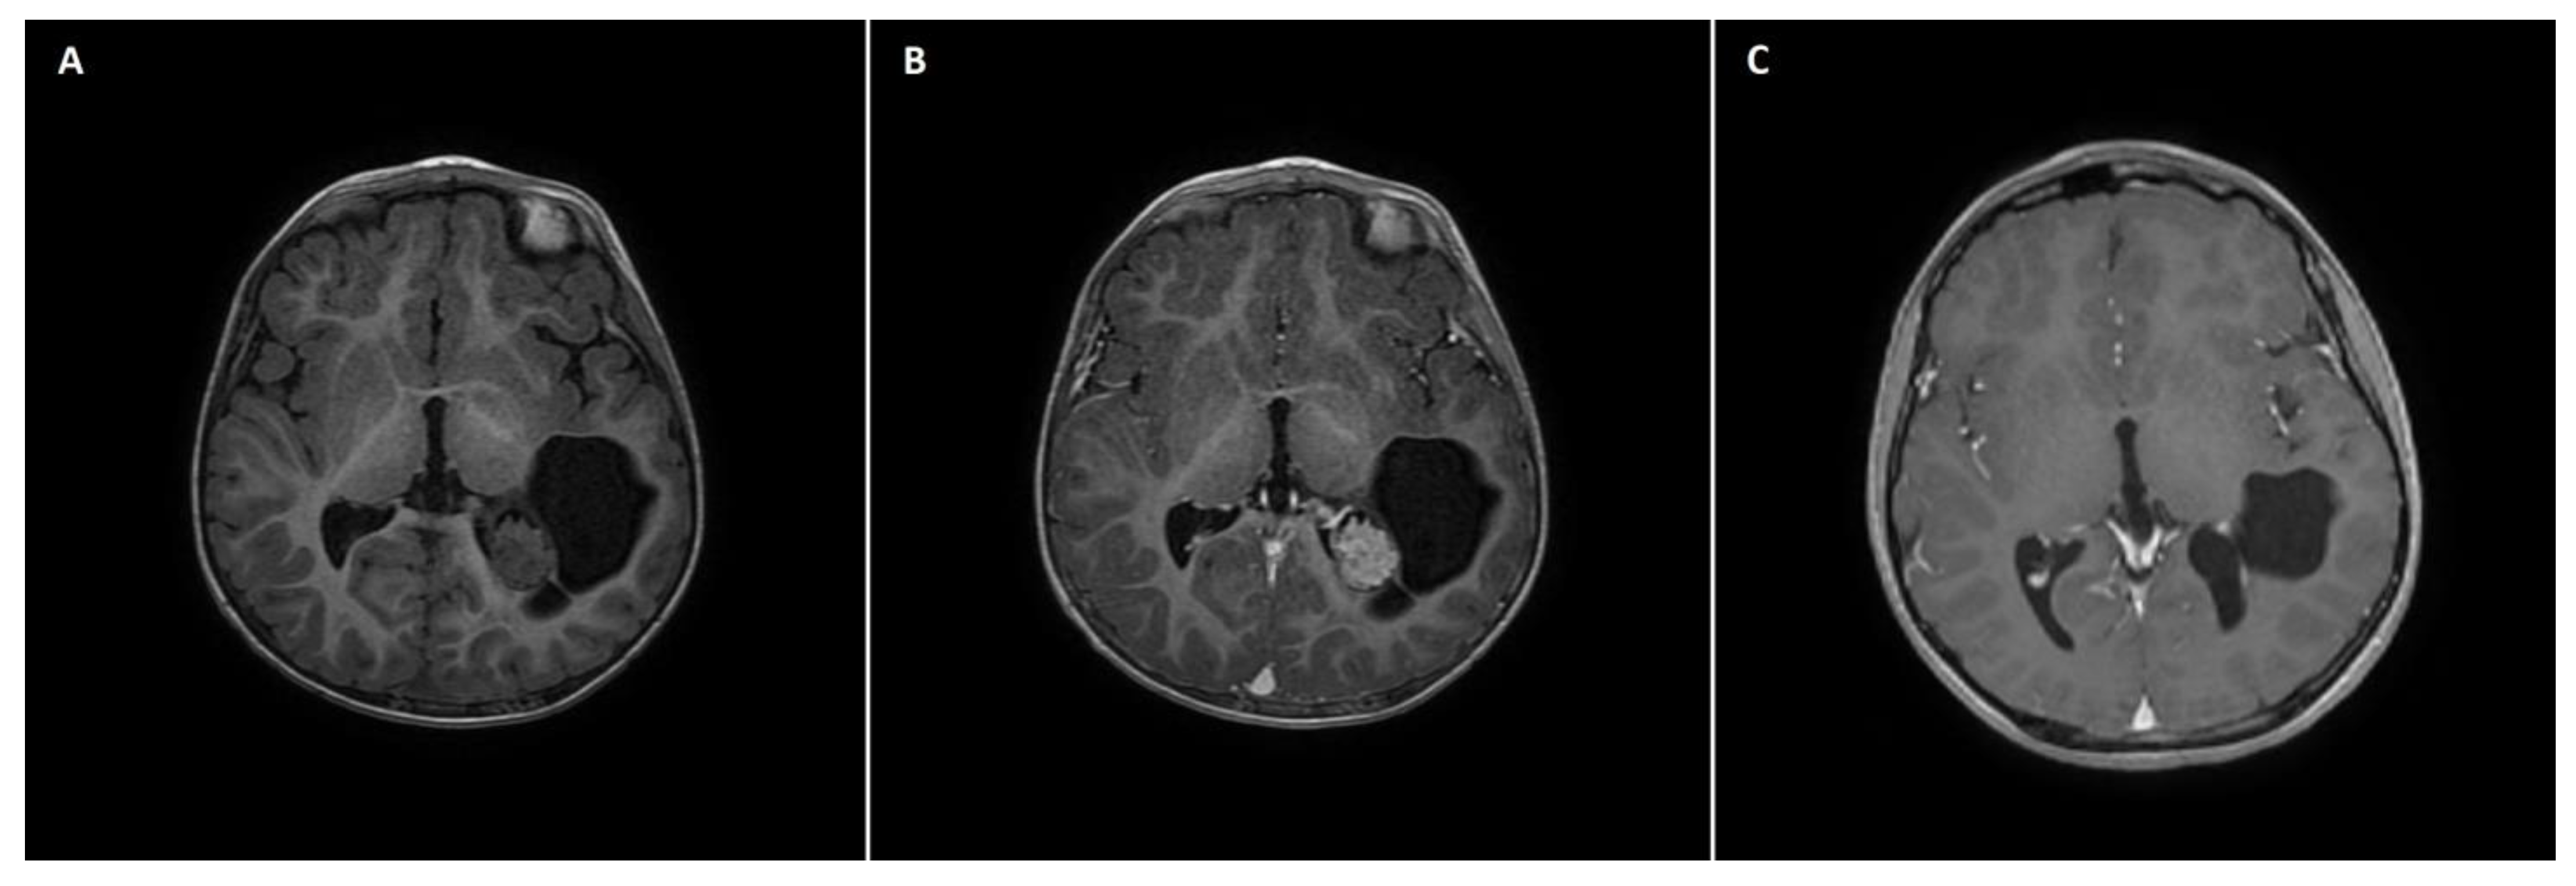

3.7. Case 4

A 21-month-old boy with a left lateral ventricle choroid plexus cyst diagnosed by means of USG in the neonatal period underwent CT and subsequent MRI due to progressive cyst enlargement. Imaging studies revealed a tumor of the choroid plexus within the left collateral triangle (Figure 2A,B). At admission, the patient was neurologically intact, with normal psychomotor development and no signs of raised ICP. Physical examination revealed slight cranial asymmetry, with bulging of the left parietal bone. The patient qualified for surgical tumor removal based on progressive enlargement of the pathologic mass. GTR of the tumor was achieved. In the early postoperative course, a few episodes of vomiting with raised body temperature occurred, but the patient remained neurologically intact. No signs of infection were detected in the blood tests. A postoperative head MRI scan confirmed complete tumor excision (Figure 2C). The patient was discharged home in an asymptomatic clinical state. Pathological examination revealed choroid plexus papilloma (WHO grade 1 tumor). The patient was followed up for 86 months with no radiological signs of tumor recurrence. Concurrently, episodes of sporadic syncope occurred clinically, but due to the lack of direct relation with surgical intervention, they were not considered to be associated with the tumor removal procedure.

Figure 2. A 21-month-old boy with choroid plexus papilloma of the left lateral ventricle. (A) A preoperative axial non-contrast T1 MRI scan with a hypodense mass located within the left occipital horn of the lateral ventricle with cystic components. (B) The preoperative axial postcontrast T1 MRI scan showed homogeneous intraventricular mass enhancement, reflective of choroid plexus papilloma. (C) A postoperative axial postcontrast T1 MRI scan reflecting complete excision of the intraventricular mass, with the remaining cystic component.